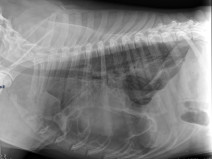

• Pyrenevet 2026 : Sur la piste du tube digestif

Nous aborderons des sujets de gastro-entérologie des carnivores domestiques. Premier motif de consultation en urgence comme en médecine généraliste, les troubles digestifs font partie du quotidien de tout vétérinaire praticien.